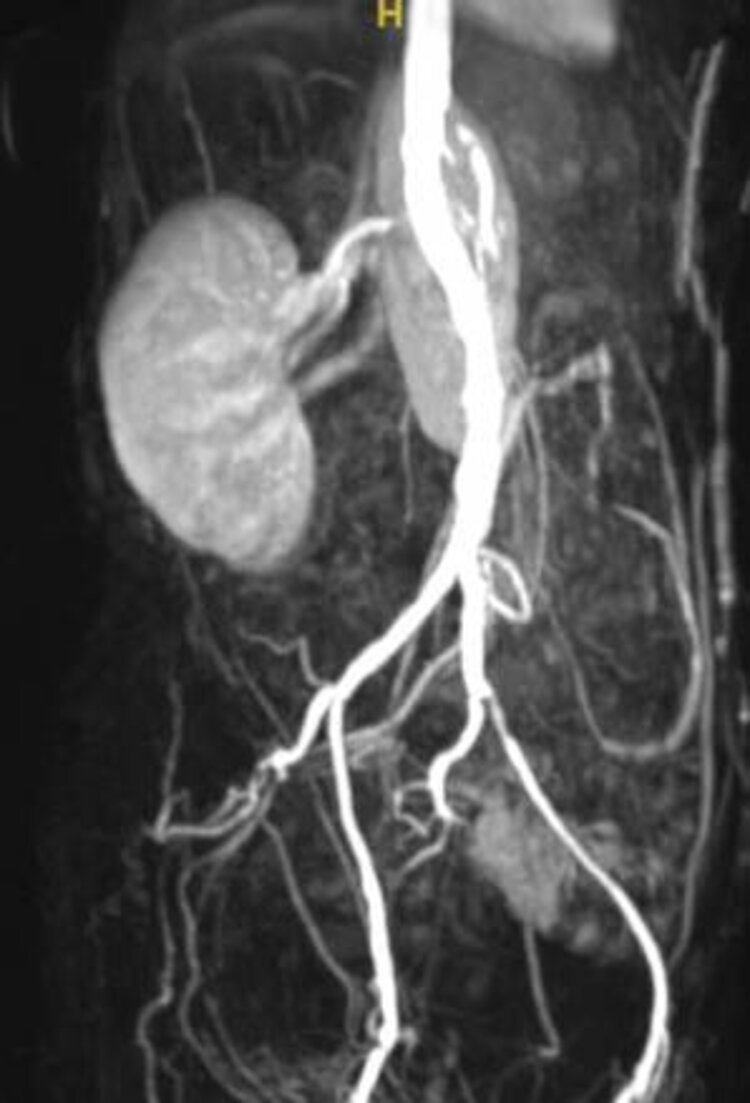

Bei der Nierenarterienstenose werden die Nieren nicht mit genügend Blut versorgt, um ihre Funktionen auszuführen. Dies kann zu Bluthochdruck, Nierenversagen und anderen schwerwiegenden Komplikationen führen. Risikofaktoren für eine Nierenarterienstenose sind u.a. Rauchen, Bluthochdruck, Diabetes und hohes Alter. Selten kommt es in jungen Jahren zu einer lokalen Gefässwandverdickung (fibromuskuläre Dysplasie = FMD) deren Ursache noch unbekannt ist. Das Beschwerdebild ist der atherosklerotisch bedingten Nierenarterien-Verengung vergleichbar.

Die Diagnose von Durchblutungsstörungen in den inneren Organen erfolgt in der Regel durch bildgebende Verfahren wie Ultraschall, Angiographie oder CT-Scans.

Die Behandlung kann je nach Schweregrad und Ursache variieren und umfasst in der Regel Medikamente und/oder interventionelle Verfahren wie die Stentimplantation oder Operationen, um den Blutfluss wiederherzustellen.